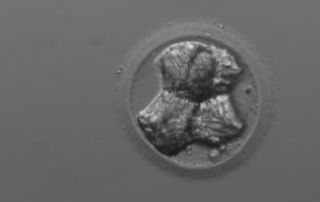

El DGP permite el nacimiento del primer bebé libre del ‘síndrome del niño burbuja’

La Fundación Jiménez Díaz de Madrid ha conseguido el nacimiento del primer varón libre de inmunodeficiencia combinada severa, enfermedad rara que afecta a 1 de cada 100.000 niños y es conocida como el 'síndrome del niño burbuja'. Eso ha sido posible gracias a la selección genética embrionaria mediante la técnica del DGP antes de realizar [...]